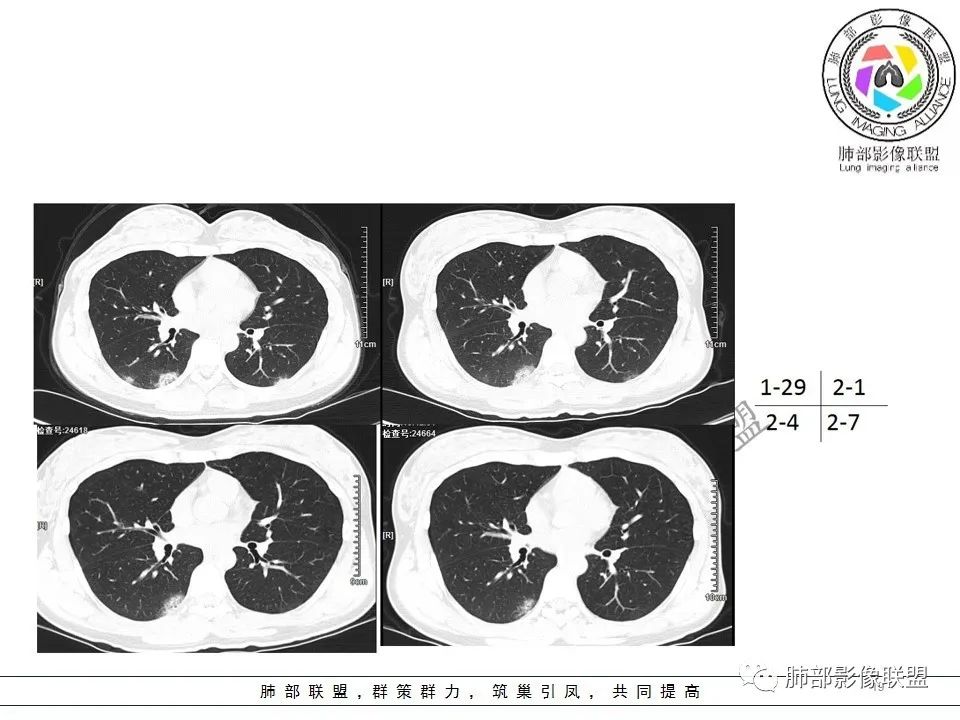

新冠肺炎早期病变影像特点

1、GGO密度偏低,不大,内部密度均匀,细网格征,边缘模糊;

2、分布上:小叶核心分布、胸膜下分布,或二者兼有;

3、内可见含气支气管征;

4、病灶如趋向于融合,长轴与胸膜平行。

1、好发部位:外围胸膜下、小叶核心区域;

2、分布特点:双侧、多发病灶,下肺多见;单发、大片叶段分布少见;

3、密度:单纯GGO或实性 GGO为主;

4、病灶长轴:病灶多横向侵犯,相互融合;长轴与胸膜平行为主,部分长轴与支气管一致; 医学百科网 | YxBaike.Com

5、病灶边缘:GGO模糊、清楚;实性病变边缘清楚、平直;

6、GGO内细网格征;

7、反晕征;

8、含气支气管征;

9、病灶内血管增粗征;

10、未见明显树芽征、空洞征、胸水;少许中央间质轻微增厚;